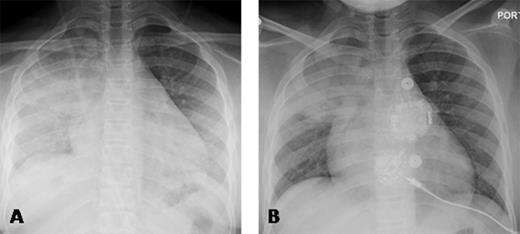

A 10 years old African American child with hemoglobin SC type SCD was transferred to our institution with fever and right upper lobe consolidation. Her respiratory rate was 23 breaths/min, SpO2 was 95% breathing room air. Serial CXR showed opacification of the entire right lung and part of the left lower lobe over a 12-hour period (Panel A). Because of the rapid progression, transfusion was recommended. However, because of the family's Jehovah's Witness religious faith, transfusion was refused.

PEG-COHb is in clinical development for the treatment of SCD and is designed to deliver preloaded carbon monoxide (CO), pick up O2, and deliver O2 to hypoxic tissue. PEG-COHb serves as a vasodilator and anti-inflammatory agent. It has been shown to have anti-sickling properties in vitro (ASH Abstract 1372, 2014). The agent was obtained from Prolong Pharmaceuticals via an emergency IND (16432) from the FDA. The agent was acceptable to the family and church elders. After written consent was obtained, 500 cc were infused according to dosing information obtained from Prolong Pharma. The CXR (Panel A) 3 hours before infusion shows opacification of the right lung and the left lower lobe. A CXR obtained one hour after infusion showed no worsening, and the CXR (Panel B) obtained 29 hours after Panel A shows significant improvement in the opacification of the lower lobes. The right upper lobe consolidation was likely bacterial pneumonia, and would not be expected to clear rapidly.

Panel A demonstrates the chest x-ray 3 hours prior to PEG-COHb with right upper lobe consolidation and evolving bilateral lower lobe consolidation and Panel B 29 hours following administration of PEG-COHb demonstrating improvement in the lower lobes.

The rapid reversal of radiographic features consistent with progressive "pure ACS" secondary to the right upper lobe infectious process suggests that PEG-COHb may be an effective treatment for sickle cell related ACS.